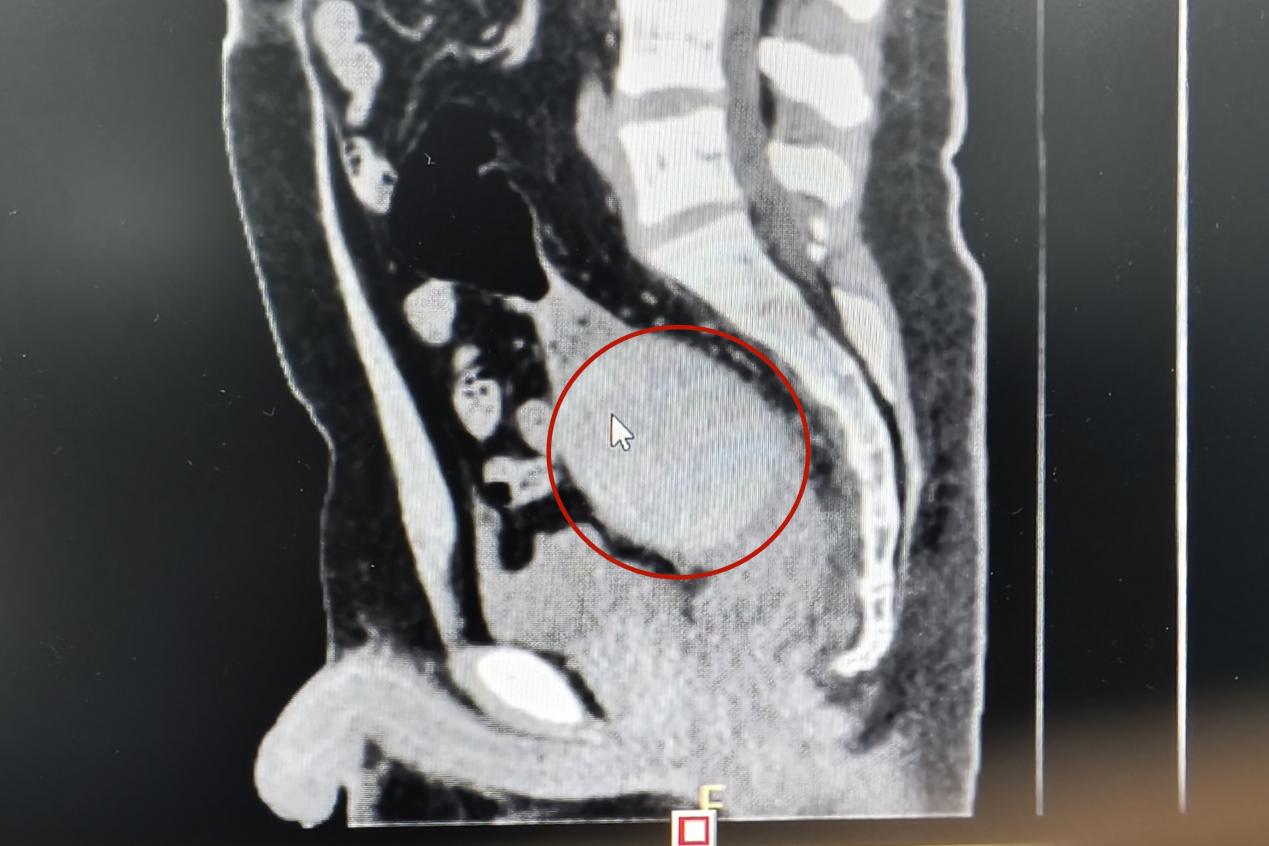

當天下午,一名青年男子來到衡陽市中心醫(yī)院肛腸外科門診就醫(yī),稱肛門內有異物,肚子疼得很。李祥樂仔細詢問病情,男子卻總是支支吾吾??此?/span>表情痛苦李祥樂便讓他躺到治療床上,對其進行了肛門指檢。“你這個異物卡得很深,指檢觸不到,需要馬上做個CT明確位置。”李祥樂一邊告知患者一邊詢問,“這個東西卡進去多久了?”得知是昨晚發(fā)生的事,李祥樂心頭一驚,卻表面平和地安慰患者道:“沒事的,到醫(yī)院來你就放寬心了,等檢查結果出來我們想辦法給你取”。CT結果顯示患者異物位于直腸與乙狀結腸交界處,位置特殊,加之卡頓時間長,取的過程中腸道破裂出血的風險隨之增加。“我可以嘗試給你經肛門取,但是如果取不出來那就需要進行腹腔手術了”。

晚上8點,患者被推進了手術室。術中,患者在麻醉后肛門括約肌松弛,李祥樂仔細探查后,用一只手從腹部壓住異物,一邊叮囑患者配合作下排動作。由于異物表面光滑,器械夾取困難,為避免患者腸壁受到損傷,李祥樂將三根導尿管插入患者肛門中,通過往囊腔中注水使得腸壁擴張,在固定異物的同時為夾取構建了通道。經過10多次反復夾取,異物被一點一點摳出,從指甲蓋大小的塊狀到整個與導尿管一起被牽拉拔出,整個手術進行了兩個小時。